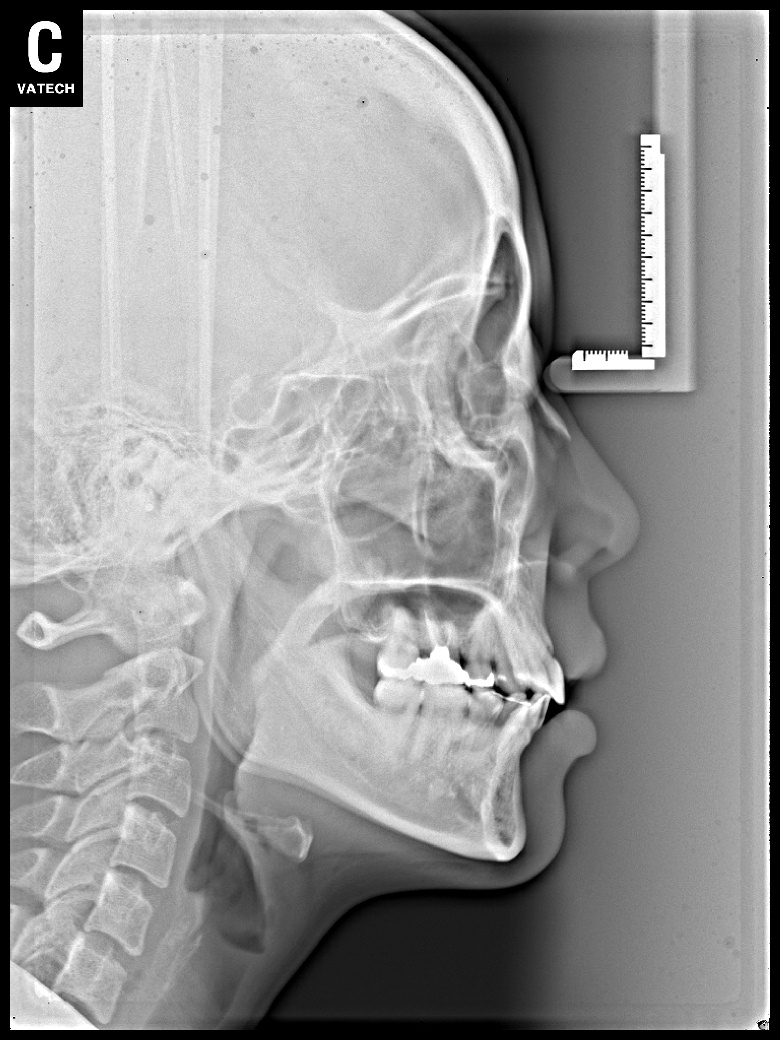

치료 전 사진입니다.